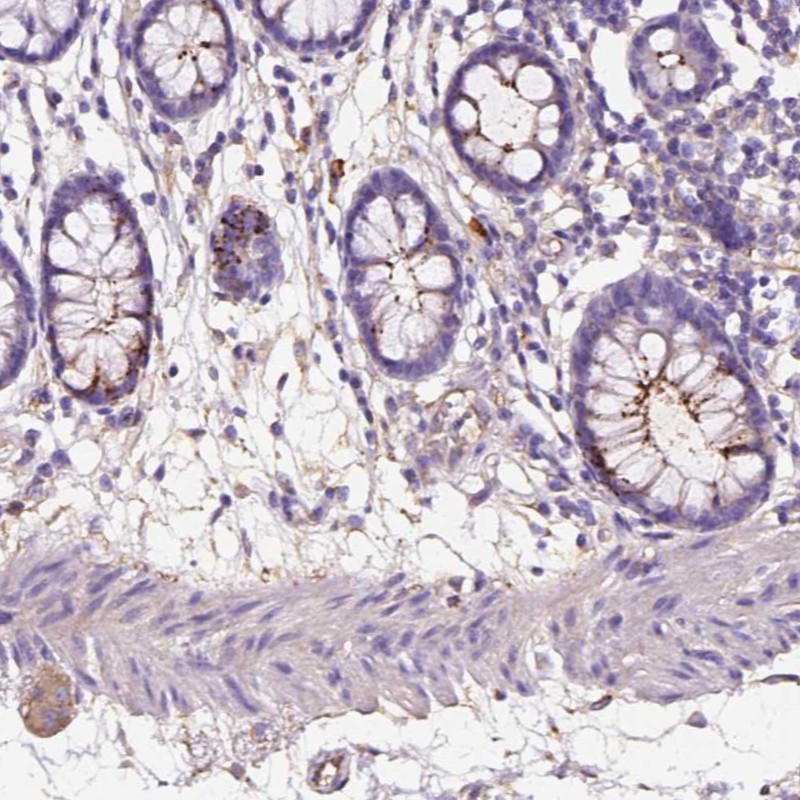

Immunohistochemical staining of human colon shows distinct membranous and cytoplasmic positivity in glandular cells while weak cytoplasmic staining in peripheral nerve/ganglion.